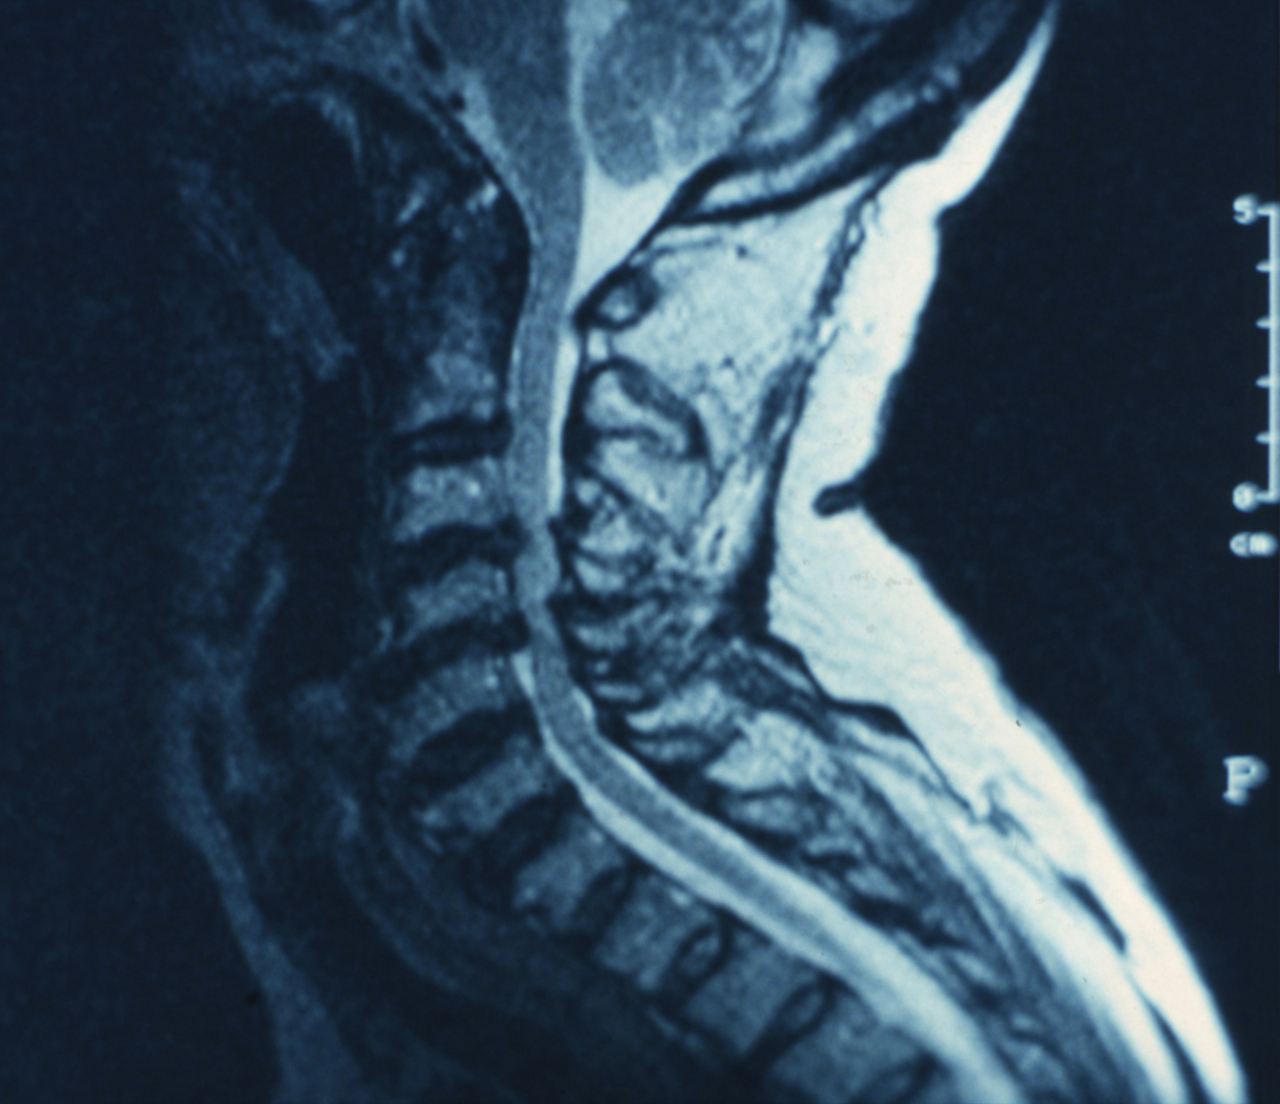

Quel est votre diagnostic ?

Il s'agit de l’aspect radiologique d’une myélopathie cervicarthrosique. La réalisation de l’imagerie par résonance magnétique est l'examen clé pour l’orientation diagnostique. La cervicarthrose, maladie très fréquente à partir de 40 ans, est habituellement responsable d’un enraidissement douloureux du cou évoluant par poussées. Ses complications sont dominées par : la névralgie cervicobrachiale, très fréquente, dont le traitement est médical ; la myélopathie cervicarthrosique par rétrécissement canalaire, responsable d’une paraplégie progressive, dont le traitement fait parfois appel à la chirurgie décompressive.